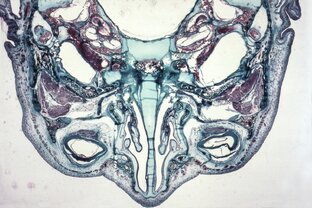

Зрение

Зрение — самый важный для всех обезьян способ чувствовать окружающий мир. Умение видеть детали и замечать отличия — жизненная необходимость. У людей существует множество индивидуальных вариантов способности видеть. Самой частой сложностью бывает нечеткость близких или далёких предметов. Человечество примерно 700 лет в этих случаях использует очки. Людей, не различающих отдельные цвета — мало, но и для них уже придуманы специальные очки. Многие млекопитающие не различают красного и зелёного В их глазах только два типа клеток: тех, что чувствуют красно-зелёный и синий свет...